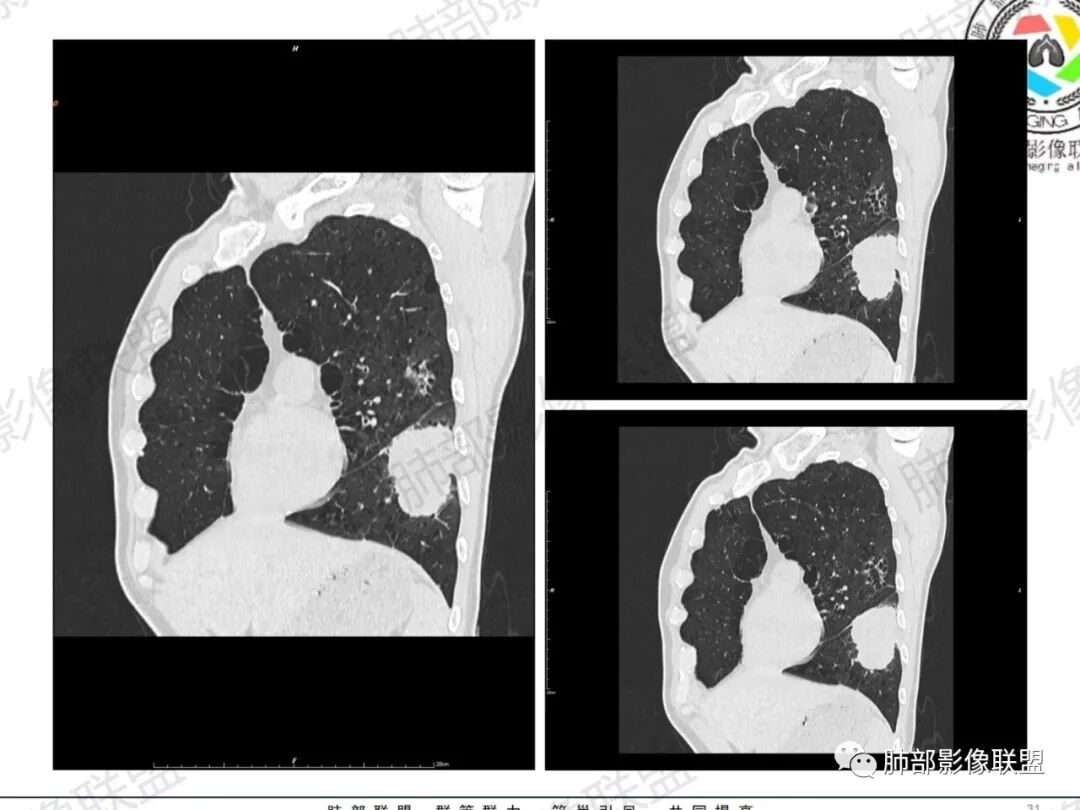

一切∮随缘:左肺下叶不规则肿块,边缘光滑,平直,局部彭隆,分叶,近端支气管堵塞,远端与胸膜相贴,平扫密度尚均匀,增强后不均匀强化,内部可见低密度坏死,胸膜下多发肺气肿,伴双肺散在光滑小结节,实验室肿瘤标志物高,考虑恶性:神经内分泌癌(大细胞),腺癌,鳞癌。

琦遇:恶性没有问题,肺气肿底子、病灶分叶、少许毛刺、叶间胸膜凹陷、部分边缘可见清晰的GGO、胸膜牵拉凹陷、局部胸水、近端支气管截断、部分支气管被推移、占位效应明显、强化特点为不均匀强化、内部有少许沼泽样低强化区,强化部分轻中强化为主、余肺可见转移性结节、左肺上叶似为囊腔型腺癌一枚,肿瘤标志物提示非小、神经内分泌,综合分析考虑大神泌、腺癌、腺鳞癌、鳞癌  同时左肺上叶囊腔型腺癌  肺转移

蕊:中老年男性,吸烟史,肺气肿背景,左肺上叶类圆形肿块影,边界清晰,边缘凹凸不平,有分叶,支气管进入阻断,临近胸膜栽赃,整体病灶膨隆,局部周围可以清晰ggo,临近叶间裂内凹,轻度强化,并可见多个低密度区,坏死可能,界线不清;肺内多结节,边缘光滑,考虑恶性伴转移,鳞癌、腺癌

傅昌瑜:中老年男性,肺气肿背景,右胸背疼痛1周。CEA、NSE、CYFRA—211升高。左上肺混合磨玻璃结节,内见较多空泡和扩张支气管。左下肺胸膜下肿块,边缘较光滑,深分叶,似有血管进入,与支气管关系不清,内见不均匀强化,见沼泽地样坏死,有胸膜栽赃。另两肺多发圆形小结节。考虑恶性并肺内转移,多原发可能性大,左上肺腺癌,左下肺病理难以判断,小细胞癌?鳞癌?

小锁:中老年男性,肺气肿背景,右胸背疼痛1周。CEA、NSE、CYFRA—211升高。左上肺混合磨玻璃结节,边界清楚,内见较多空泡。左下肺肿块,边缘清楚,深分叶,有血管和支气管进入,胸膜凹陷。另两肺多发圆形小结节。考虑双发原位癌,左上肺腺癌,左下肺大神泌或腺鳞癌可能,肺内转移。

蓝天白云:中年男性,肺气肿背景,左肺下叶肿块,边缘膨隆,有分叶,内有湖泊样坏死,有轻中度强化,局部胸膜栽赃,收缩力不强,周围见肺气肿征象。左肺上叶混合磨玻璃影,边界清楚,考虑都是恶性,左上肺iac,左下肺腺鳞癌,或大细胞肺癌可能。两肺多发结节,考虑转移

毛勤香:老年男性,肺气肿背景,左肺下叶肿块,分叶,边缘光滑,土豆块样,细支气管闭塞,增强轻度不均匀强化,似有坏死,左肺另见多发结节,淋巴结未见明显肿大,恶性确定,吸烟史,鳞癌破坏力强,侵袭力差,多原发的一般很少多于3个,故排后,首先考虑神经内分泌癌,局部血管穿行,鉴别淋巴瘤

周太狼:中年男性,吸烟、高血压史,肿瘤指标升高,肺气肿背景下,左肺下叶肿块影,分叶、膨隆、未跨叶裂,支气管截断,不均匀强化。另双肺多发结节及磨玻璃影,左肺上叶混合磨玻璃,内可见多发空泡影。整体考虑恶性,肺癌伴肺内转移,左下肺鳞癌?神经内分泌癌?左肺上叶囊腔腺癌?